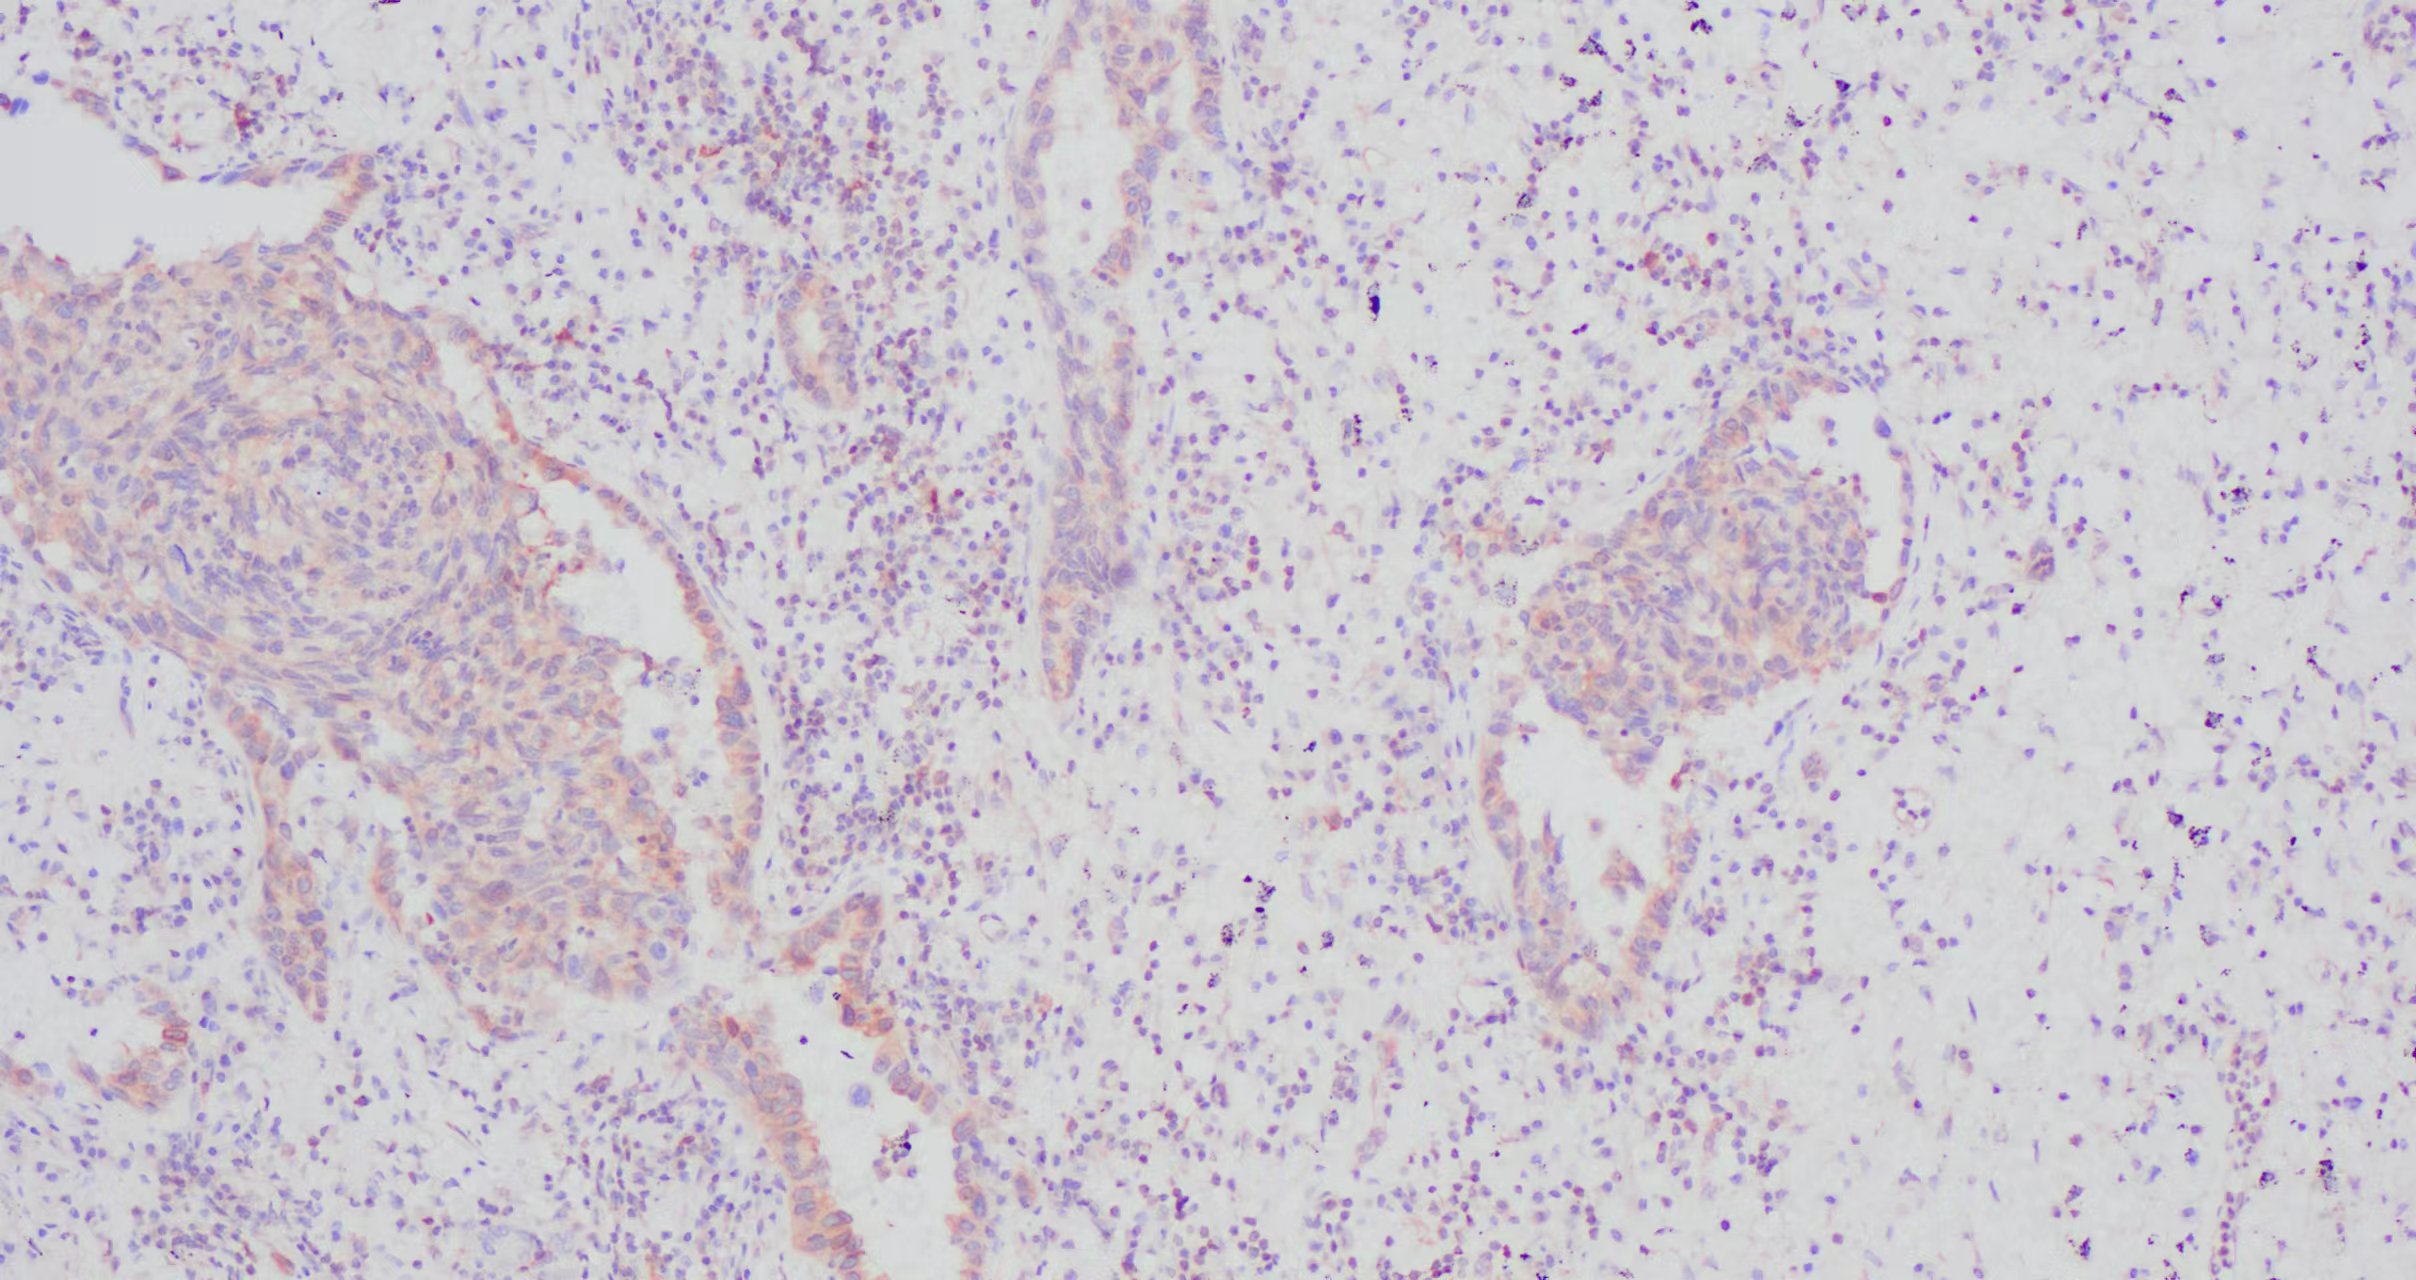

您的位置:首页 >> 产品介绍 >> IKBA 免疫组化

IKBA  肺癌组织

IKBA  肺癌组织2.jpgIKBA  肺癌组织2.jpg

IKBA 肺癌组织1.jpg